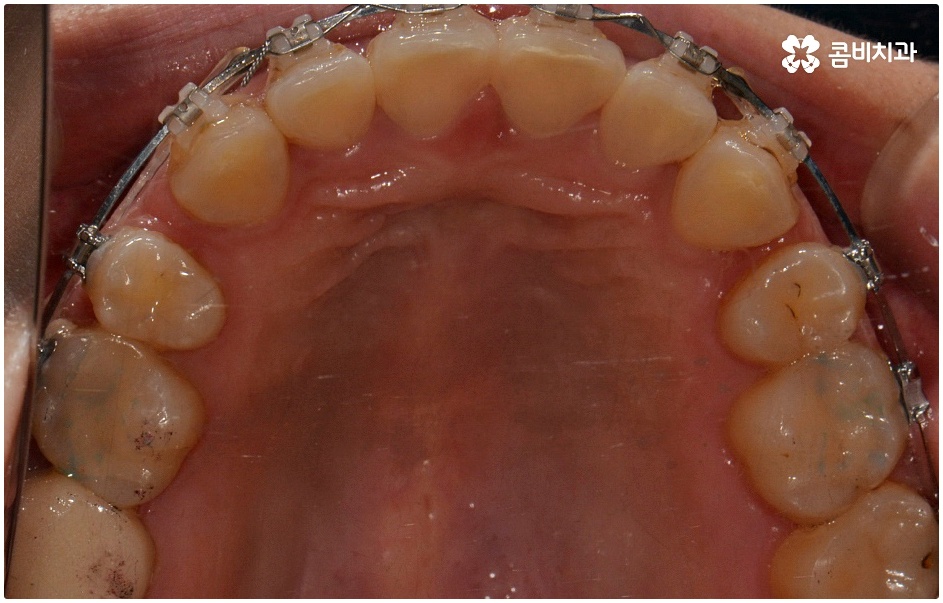

치료를 위해서는 입을 안쪽으로 넣기 위한 공간을 확보해야 하므로 보통 위아래 소구치 총 4개의 치아를 발치하여 그 공간을 활용해 튀어나온 치아와 잇몸을 전체적으로 뒤로 이동시키는 방법을 사용하나 최근에는 미니스크류, 치간 삭제 등의 방법을 이용하여 비발치 교정을 진행하기도 하니 먼저 자신의 상황을 꼼꼼하게 살펴보고 부정 교합의 원인과 정도부터 정확하게 파악하는 것이 필요한 거에요.

또한 골격성으로 유발된 문제의 경우 치료가 끝나고 사후 관리를 제대로 하지 않으면 다시 원래대로 돌아가려는 힘이 강하니 주기적으로 체크를 하면서 교정 유지장치를 일정 시간 이상 꼭 착용하시는 것을 권유드리며 탈착식 외에 치아 뒷면에 얇게 부착하는 방식의 유지 장치도 있으니 담당의 선생님께 문의해 보시고 각자에게 맞는 것으로 사후 관리를 철저하게 해 주시길 바라고 있습니다.